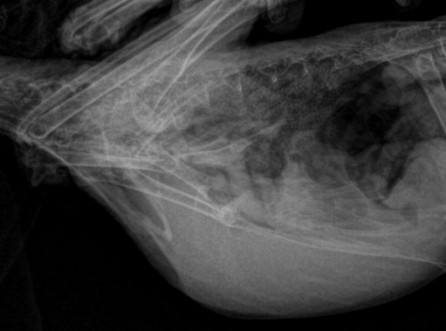

토끼 방광결석 수술